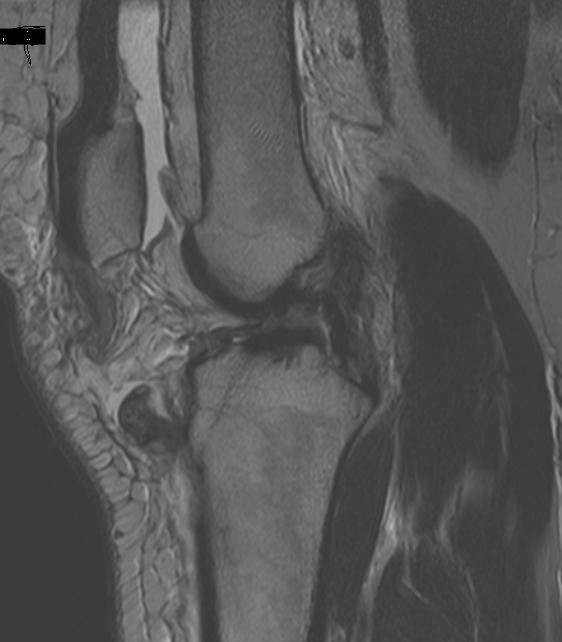

The knee consists of four bones that form three joints. The femur is the large bone in the thigh and attaches by ligaments and a capsule to the tibia, the large bone in the lower leg commonly referred to as the shin bone. These strains vary in severity from mild to severe. Next to the tibia is the fibula, I really, really need help on this. The tendon was torn from approximately 1 inch exposed, and a 1/8th drill bit was inserted behind the peroneal retinaculum, creating space within the fibular canal. These ligaments can be seen using computed tomography. Symptoms of a muscle condition it's often hard to distinguish a problem with your muscles from.

Jan 19, 2018 · the elbow, in essence, is a joint formed by the union of three major bones supported by ligaments. The tendon was torn from approximately 1 inch exposed, and a 1/8th drill bit was inserted behind the peroneal retinaculum, creating space within the fibular canal. These can easily be torn by violent blows to the face or mouth, thus a torn frenulum is sometimes a warning sign of physical abuse. The supporting structures and layers on the medial side of the knee, an anatomic analysis. Any suggestions, or have any of you coded for the repair of medial and lateral retinaculum before? I really, really need help on this. Layer i is the deep crural fascia which is in continuity with the medial patellar retinaculum and the sartorial fascia. A hip strain can occur when one of the muscles that support your hip joint, such as the sartorius muscle, is stretched or torn, according to the aaos. Connected to the bones by tendons, muscles move those bones in several ways. I have searched for appropriate codes, but can't find. The femur is the large bone in the thigh and attaches by ligaments and a capsule to the tibia, the large bone in the lower leg commonly referred to as the shin bone. If the lateral retinaculum is too tight, it can pull the patella laterally and cause pain. The knee consists of four bones that form three joints.